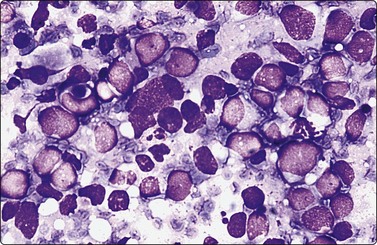

Plasmacytoma (Figs 5.35, 5.36)9,69,146,147

image

Fig. 5.35 Plasmacytoma

Pure population of well-differentiated plasma cells (MGG, HP).

Fig. 5.36 Myeloma in lymph node

Poorly differentiated plasma cells. This patient had multiple myeloma (Pap, HP).

Criteria for diagnosis

1 cells resembling mature or immature (nucleoli-containing) plasma cells,

2 eccentric nuclei, condensed chromatin or blastic-like, condensed cytoplasm,

3 immunophenotype: CD38, CD79a, CD138, OCT-2, CIg; CD 20 and Pax 5 very often negative,

4 aberrant immunophenotype: CD56, CD10, CD117, cyclin D1.

Be wary of unusual cellular morphology, e.g. occasional cases dominated by pleomorphic, signet ring, clear and sarcomatoid cells, which may be difficult to recognize as plasma cells. The rare variant with a small lymphocyte-like morphology may mimic a B-cell lymphoma.